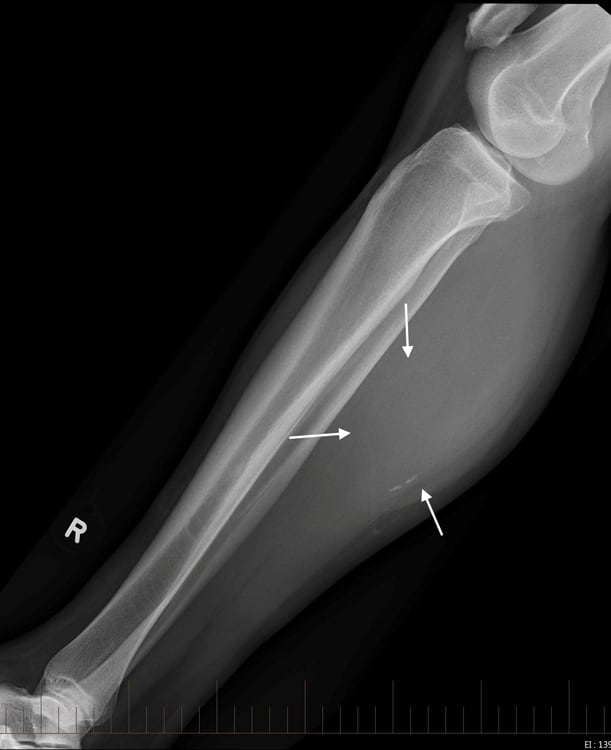

Tụ máu cẳng chân

» Thông tin: Nam giới – 41 tuổi.

» Lâm sàng: Sưng đau cẳng chân / Chấn thương cẳng chân 15 năm.